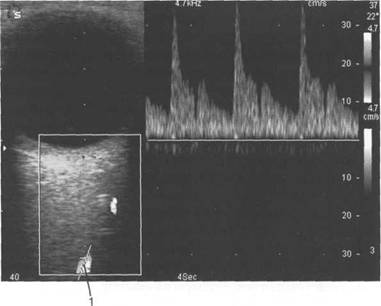

При сонографии отчетлив 121h711b о выявляется чивается хрусталиком, а сбоку - ресничным

нии 10-15 мм от склеры (рис. 2.21,